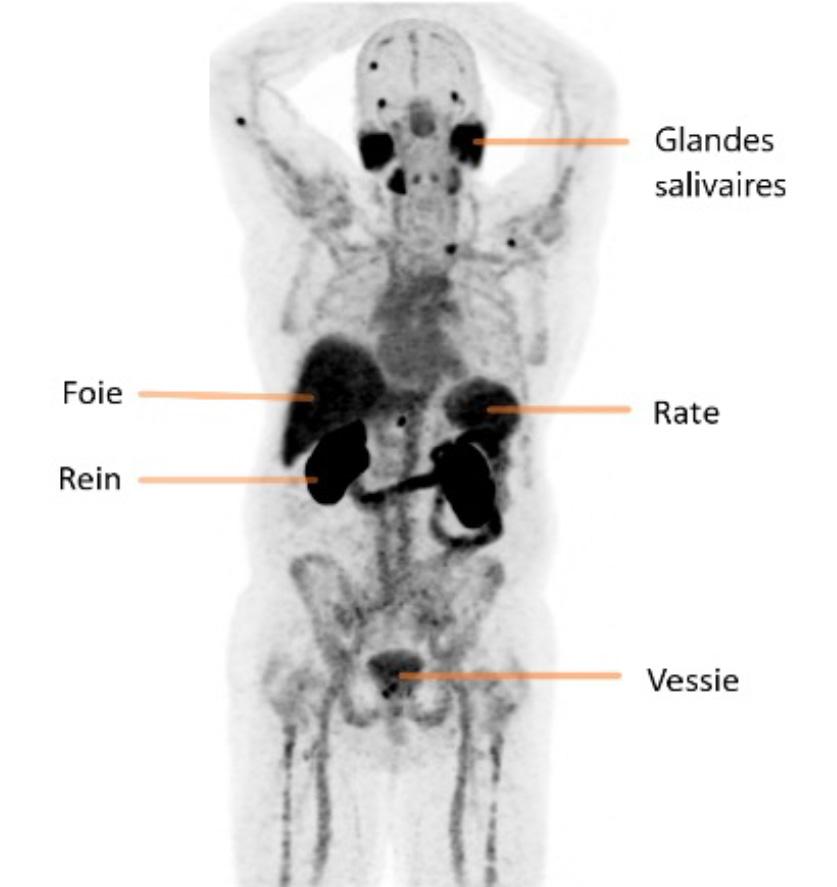

Le foie, les reins, la rate, les glandes salivaires et lacrymales, le duodénum et l’intestin grêle ainsi que la vessie sont des structures normalement visualisées lors d’un TEP au Ga68-PSMA. (Figure 2)

Aux figures 3 et 4, nous pouvons voir le même patient en TEP Ga68-PSMA et TEP F18-FDG avant le début des traitements. Sur la figure 5, nous avons le même patient environ 3 mois après la fin de ses 6 cycles de traitements.